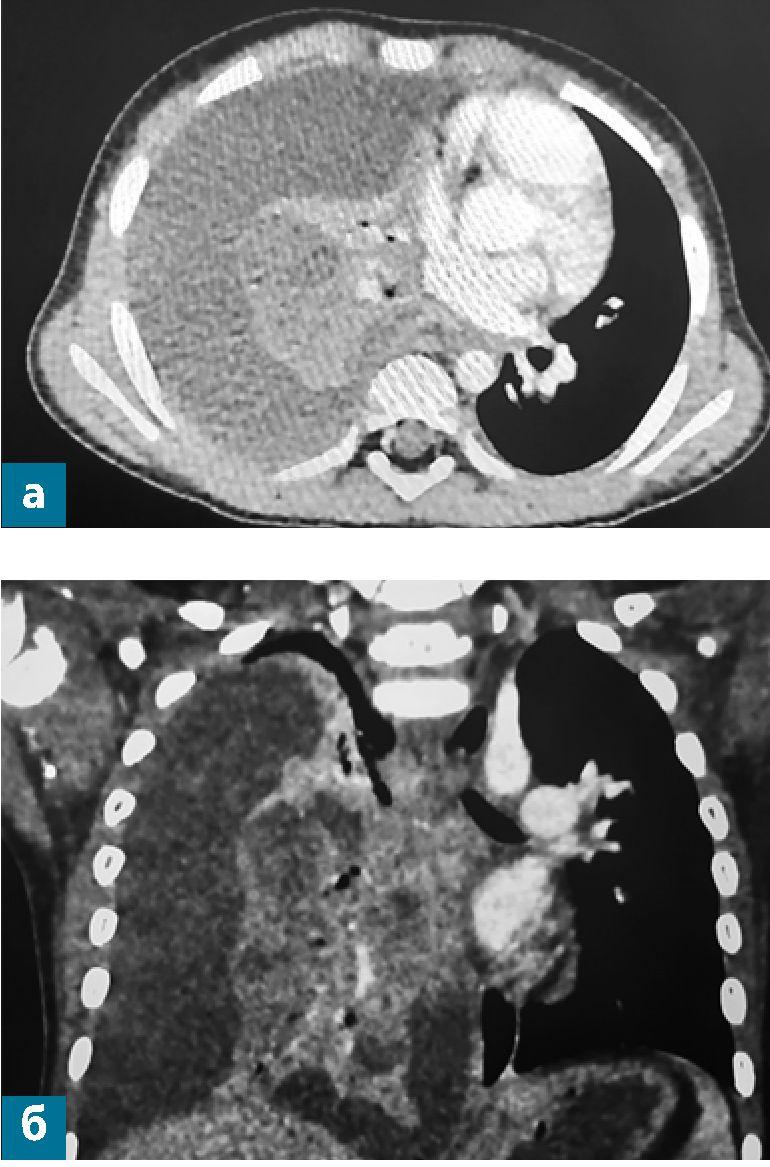

Результаты ультразвукового исследования по существу подтвердились после получения данных компьютерной томографии органов грудной клетки с контрастным усилением, проведенной на следующий день (рис. 3).

Рис. 3. Компьютерные томограммы органов грудной клетки мальчика Б. на пятый день болезни (нативное исследование и с контрастным усилением) в аксиальных плоскостях

На полученных томограммах толщиной среза 1 мм и мультипланарных реконструкциях до и после контрастирования «Омнипак 300»:

- Слева: на уровне нижних отделов косой щели (на границе 5 и 8 сегментов, прилегая к диафрагме) определяется округлой формы образование, диаметром 15 мм в аксиальной плоскости, с четким неровным контуром, КТ-плотностью +54 HU, в центре участок гиподенсивной плотности, +19 HU, размером до 7 х 7 мм. Определяется утолщение междолькового интерстиция в 5 сегменте и нижней доле легкого, субплевральное неравномерное уплотнение легочной ткани в 9 и 10 сегментах.

Жидкость в левой плевральной полости по задней поверхности нижней доли до 7 мм.

- После контрастирования определяется накопление контрастного вещества в капсуле образования до +110 HU, в центральных отделах контраст не накапливается.

Заключение: КТ-картина может соответствовать абсцессу левого легкого, перисциссуриту слева. По-лисегментарная пневмония слева, жидкость в левой плевральной полости.

Рис. 5 (а, б).Компьютерные томограммы органов грудной клетки мальчика М. на десятый день болезни в аксиальной и фронтальной плоскостях с контрастным усилением.

Заключение: КТ-картина правосторонней деструктивной пневмонии, с массивными зонами ишемии, множественными полостями и коллаби-рования легкого, вызванного массивным плевральным выпотом справа (рис. 5).